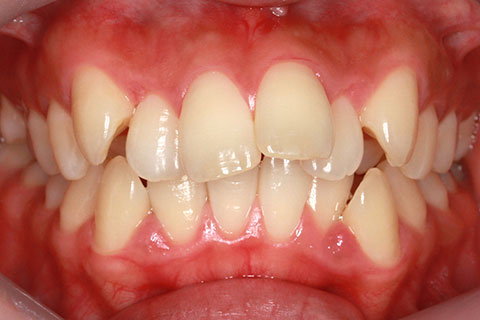

ハーフリンガル矯正3:上の歯のみ舌側矯正で治療(矯正期間24ヶ月)

治療前

治療中(開始直後)

治療中(開始半年後)

治療後

- 年齢・性別

- 25歳女性

- 治療期間

- 2年0ヶ月

- 抜歯

- 上下4番抜歯

- 治療費

- 110万円

- 治療内容

- 施術の副作用(リスク)

- 表側矯正と比較して、力学的な操作性が複雑なため、ボーイングエフェクトを起こしやすい。